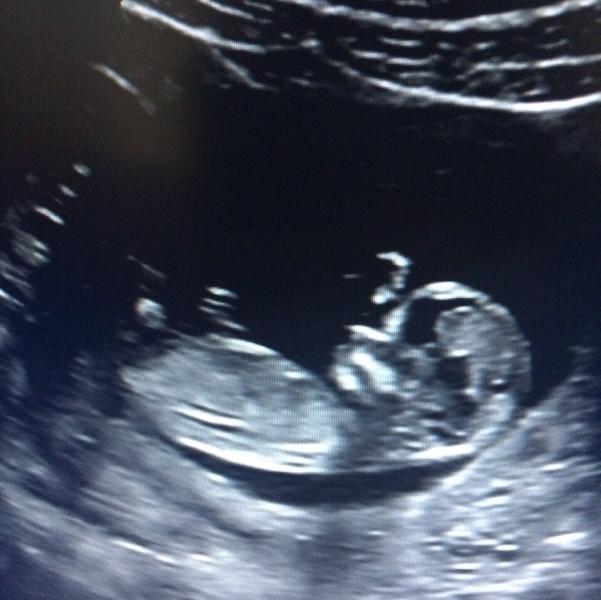

😍😍😍😍😍😍😍😍😍 Это просто запредельное милейшество!!!!🙈 Здоровья Вам!💐💝💐💝💐💝

@marysia77, и я на первом прослезилась, хотя не эмоциональная... А сердечко до сих пор с восторгом слушаю)))

@germion4ik, да, я всплакнула и сердечко впервые услышала, это невероятное чудо! 😊